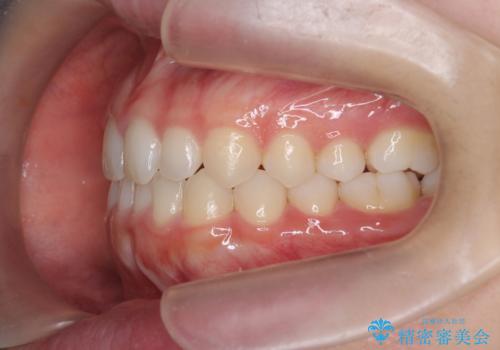

前歯のガタつき・ねじれを治すマウスピース矯正

- 前歯のねじれ、ガタつきを改善し綺麗な歯並びにしたいと希望され来院されました。

マウスピース矯正インビザラインによる矯正治療を計画しますが、マウスピース矯正で治りにくい歯のねじれを事前にワイヤー矯正でしっかりとなおしておくことで矯正治療期間の短縮できるような治療計画を立てます。

マウスピース矯正を始める前にワイヤー部分矯正を行ったことで改善のしにくい歯のねじれをしっかりと治すことができました。